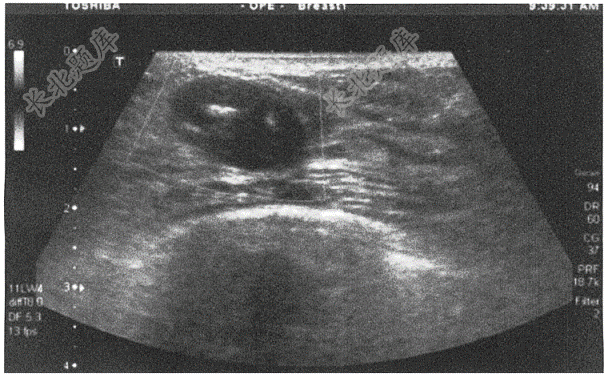

- 简答题青年女性,28岁,因发现右乳肿物1周入院。患者右乳内上象限可见2×3cm肿物,质硬,活动度可,行B超如下图,请进行简单描述和写出主要诊断

- 青年女性,28岁,因发现右乳肿物1周入院